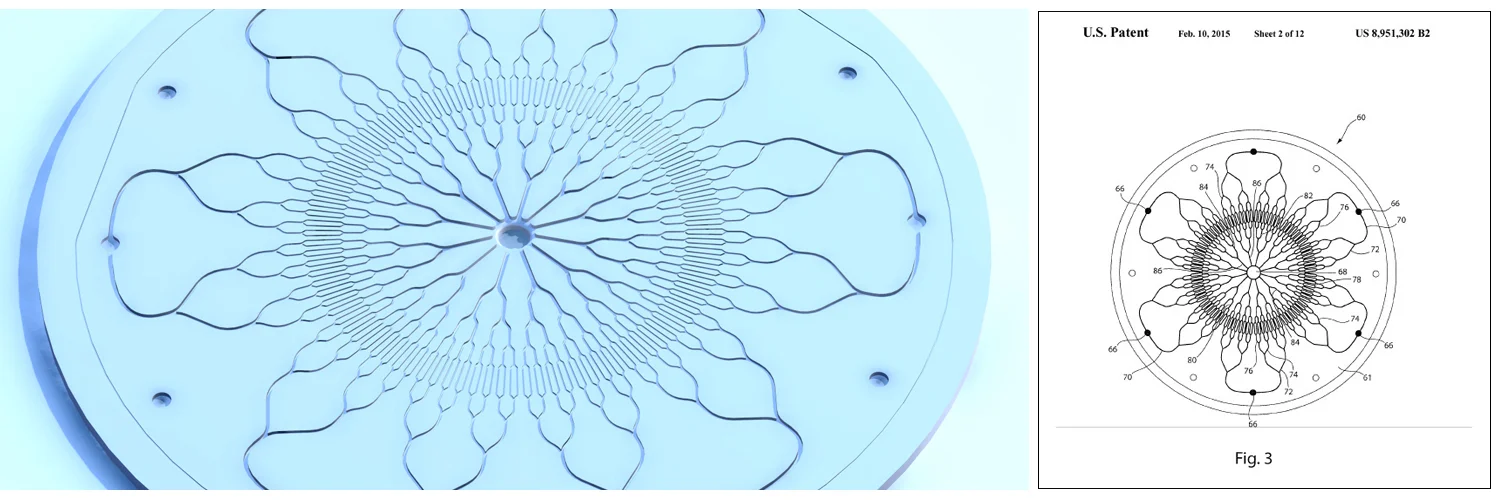

Implantable Device for Assisting Human Liver Function

BioEngine Inc

Primary mechanical engineer designing and developing an implantable microfluidic device for assisting human liver function. Developed while at BioEngine Inc which was an early-stage medical device company. Worked closely with surgeons and biologists at Massachusetts General Hospital who collaborated with BioEngine on the project.

- Is an implantable silicone based device which includes a microfluidic channel network. A novel approach was used to prevent blood flowing through the system from clotting.

- Designed and fabricated prototypes of the device for bench-top testing. Assisted with preclinical porcine studies.

- Iteratively refined the fluid system with computational fluid dynamics (CFD) software.

- Blood in the channel network interacts with human liver cells through a microporous membrane.

- Published research in the Journal of Tissue Engineering: “Principles of Biomimetic Vascular Network Design Applied to a Tissue-Engineered Liver Scaffold”

- Patent #8951302, “Biomimetic vascular network and devices using the same”